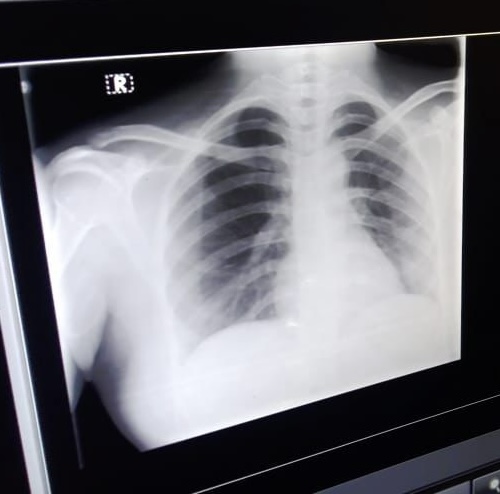

Respiratory System-